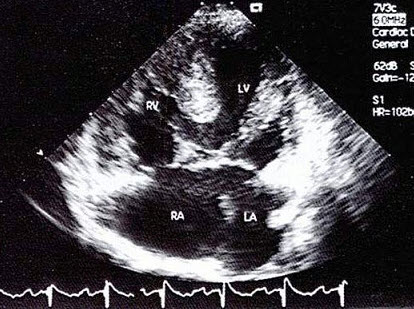

5、单项选择题

如图,初步超声诊断为()

A.二尖瓣返流

B.三尖瓣返流

C.主动脉瓣返流

D.肺动脉瓣返流

E.以上均不是